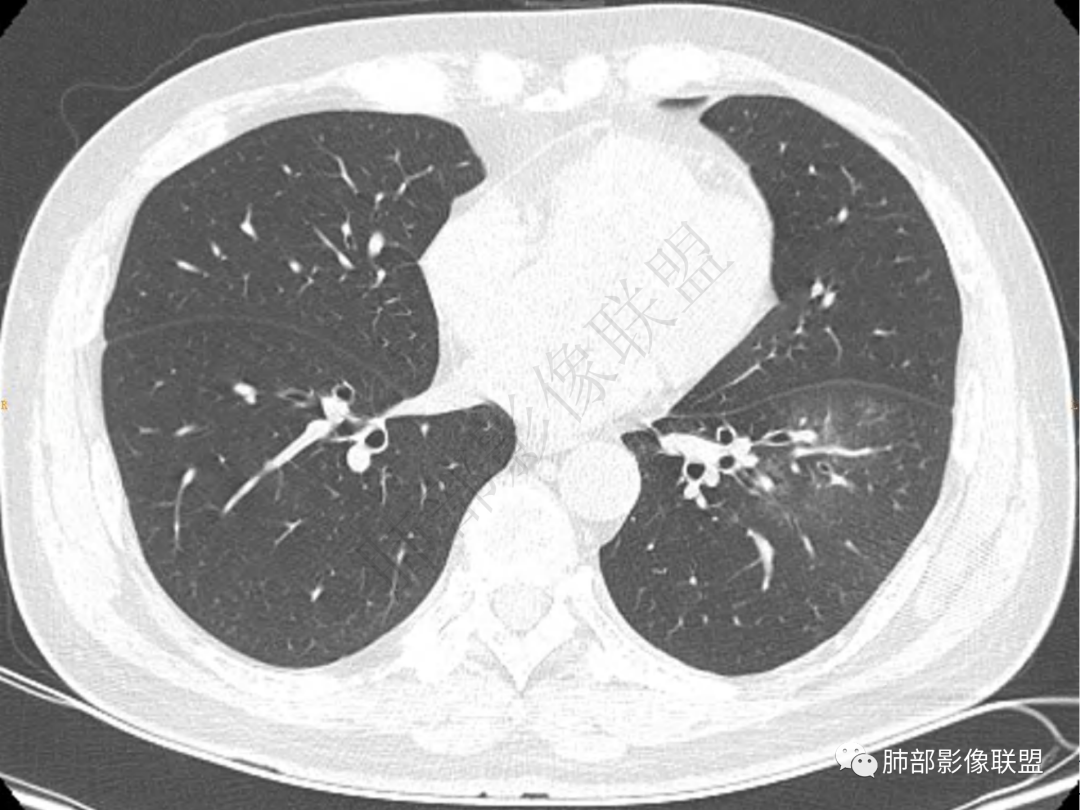

2.左肺下叶团片影,跨背段及内前基底段,实性部分类椭圆形,密度不甚均匀,可见毛刺及棘状突起,未见典型分叶及胸膜凹陷。病灶上下缘可见相应肺段支气管旁进侧出,管壁轻度增厚,未见狭窄阻塞。

3.周边较大范围磨玻璃影,边界相当模糊,小叶增厚明显。注意叶裂另一侧、左肺舌段亦可见磨玻璃影及增厚的小叶间隔。未见明确卫星病灶。

4.实性部分不均匀环形强化并显示一小范围低密度坏死区或空洞。较之肺窗,整体纵隔窗范围较小,提示病灶并不十分密实。抑或为不同时段图像。

5.双肺门及纵隔未见增大淋巴结。未见胸腔积液。

1.病灶不够密实,没有典型分叶,收缩乏力等,支气管未见截断等,缺乏一般肿瘤性肿块特征。

2.周围磨玻璃影边界不清缺乏限制,甚至“激惹”到相邻肺叶,也许提示较明显的炎性水肿。